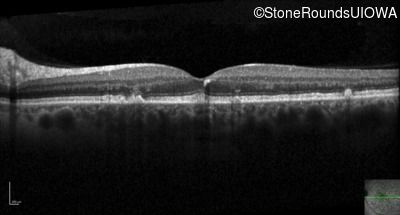

Optical Coherence Tomography - Right - 20/20 -1 sc

Exemplar / OCT Stack